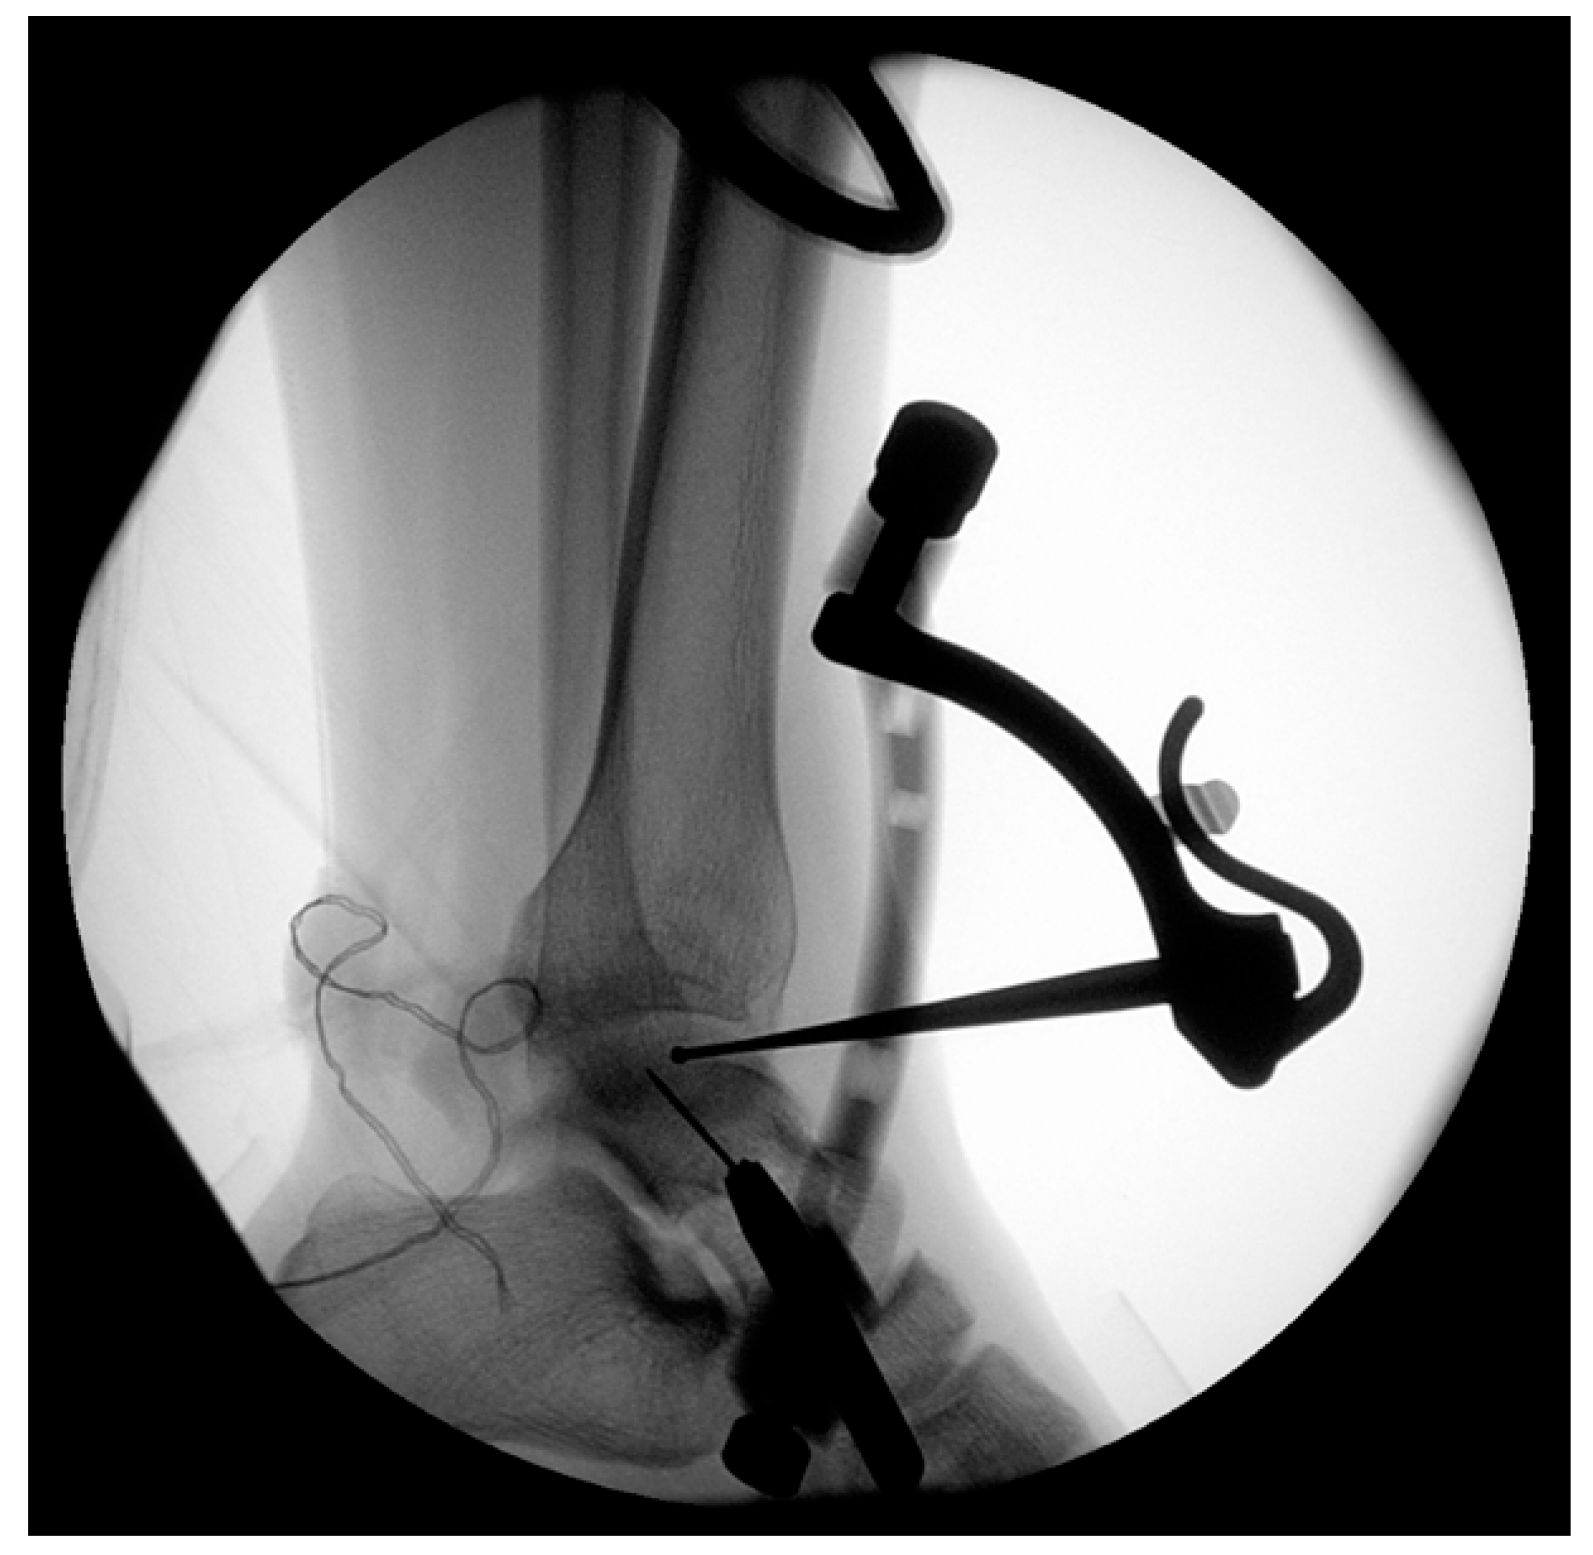

2.2. Surgical Techniques